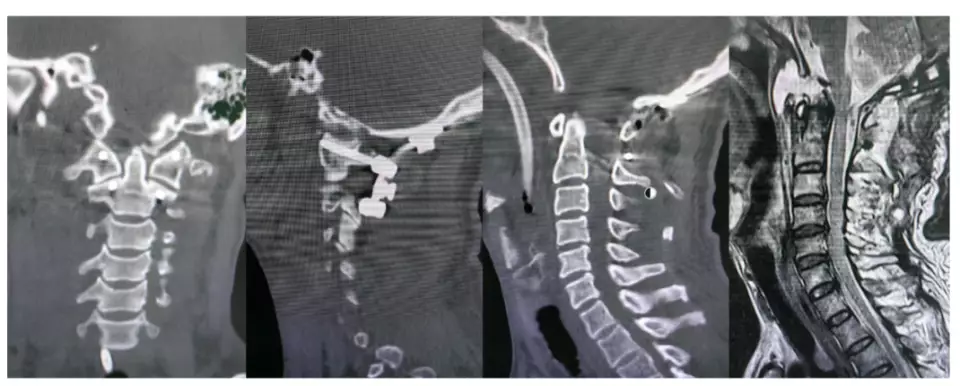

人妻在丈夫結紮9個月後被診斷出懷孕怒斥醫院手術失誤追討賠償。資料圖片

近日,河北一名女子投訴保定京濟醫院指,丈夫於該醫院接受輸精管結紮手術9個月後,自己竟懷孕,懷疑手術出現問題,遂要求院方承擔流產、營養及誤工等相關費用。女子出示丈夫手術當日的精液檢測報告,顯示樣本中仍含有精子,事件引起社會廣泛關注。

醫院承認部分責任

11月12日,院方醫務科人員回應指,女子於11月6日持懷孕報告前往醫院反映,經核實,對方丈夫於今年2月接受手術。院方稱:「既然發生了這個事,醫院肯定要解決問題。昨天(指11日)她愛人做的精液常規顯示有精子,我們確實有責任」。

院方指患者未遵醫囑 雙方仍就賠償談判

不過,醫務科人員表示,手術後患者需每月檢驗精液連續三次,確認無精子方可保證手術成功,然而對方並未依醫囑定期檢查,「做完手術後大夫會給一張術後注意事項卡片,交代了隔一個月要查一次精液常規,連續查三次確定沒有精子了,才能保證這個手術是成功的。但我們記錄里,患者沒有來我們醫院復查,也不能提供在其他醫院做的檢查報告。」目前,雙方正就賠償事宜進行溝通,該女子早前於社交平台發布的相關貼文已被刪除。